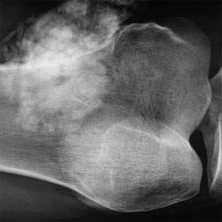

(Слева) Рентгенография в боковой проекции: множественные костные островки, которые также присутствовали в других областях. Такое состояние именуется остеопойкилозом и не требует дополнительного обследования.

(Слева) Рентгенография в ПЗ проекции: типичный крупный костный островок. Равномерный участок склероза с краями в виде щетки, которые переходят в нормальную кость. Четкий склерозированный край отсутствует.